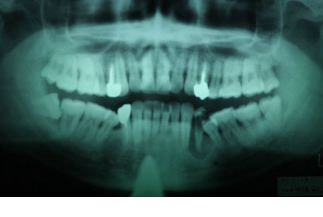

問診・視診・打診・温度診・レントゲンなどの検査を行っても原因が特定できない場合でも、マイクロスコープで検査を行うことで何が原因になっているか特定できる症例はたくさんあります。